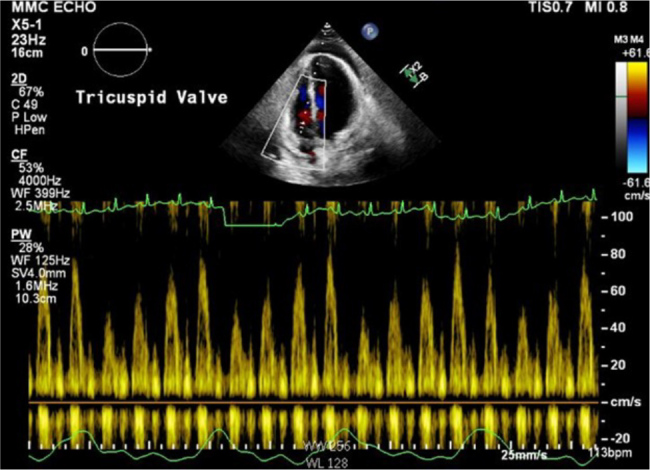

Case description: A 24-year-old female with cystic fibrosis, diagnosed at nine months, presented with two weeks of dyspnoea. Examination revealed bilateral rhonchi, facial oedema and non-pitting thigh oedema. Laboratory results showed a white blood cell count of 11.3 ×109/l, erythrocyte sedimentation rate of 99 mm/hr and C-reactive protein level of 45.3 mg/dl. Initially admitted for cystic fibrosis exacerbation, she was found to have pericardial effusion. Despite facial and lower extremity swelling, she denied cardiac symptoms. During hospitalisation, she developed haemodynamic instability requiring pericardiocentesis, with echocardiography confirming constrictive pericarditis. Chest computed tomography angiography showed pericardial calcifications; autoimmune workup was negative. She was discharged on colchicine with close follow-up.

Abstract Image